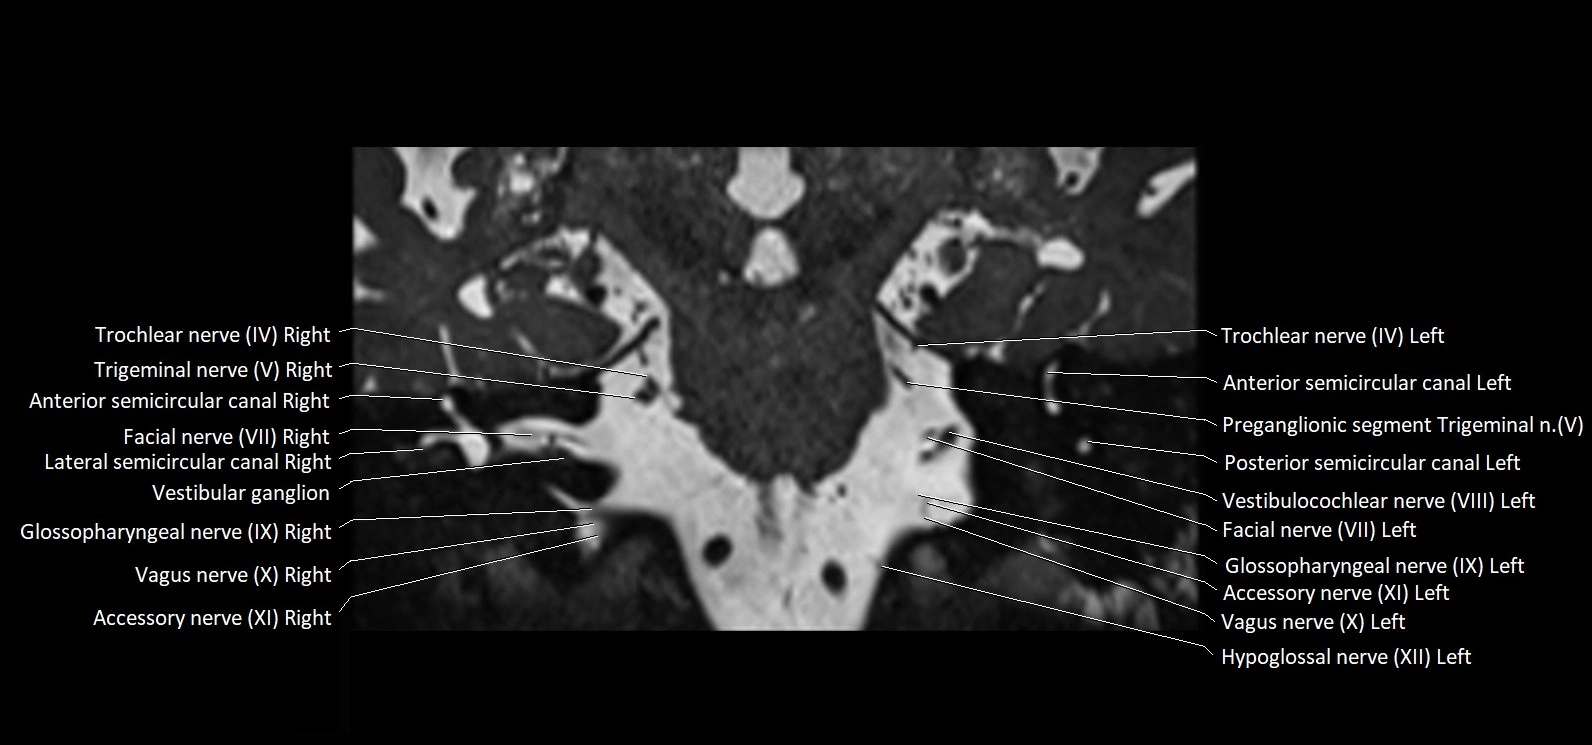

MRI Appearance

• The abducens nerve is a small, thin, linear structure

• Best visualized on high-resolution T2-weighted 3D MRI sequences (e.g., FIESTA or CISS)

• Seen as a hypointense (dark) line running from the brainstem at the pontomedullary junction, traversing the prepontine cistern, and entering Dorello’s canal under the petrosphenoidal ligament, then into the cavernous sinus, and finally the orbit

• May be challenging to visualize in standard MRI due to its small size

• Pathology may be inferred by absence, displacement, or enhancement of the nerve

MRI images

image